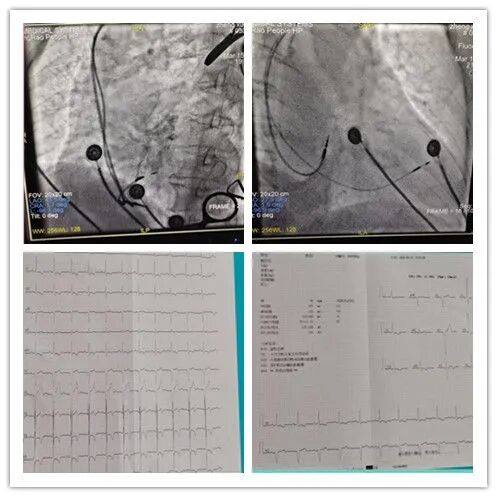

手術(shù)當(dāng)天,劉裕忠和賀騫細心準備,謹慎操作,在專用電極的影像參考下選擇合適位點,再擰入起搏導(dǎo)線至深間隔,成功完成左束支電極的植入。經(jīng)測試左束支電極各項參數(shù)良好,單極閾值0.9V,感知9.1mV,阻抗978ohm,達到左束支起搏參數(shù)要求,QRS波寬度術(shù)后為114ms?;颊呱w征平穩(wěn),無手術(shù)并發(fā)癥,術(shù)后各項參數(shù)良好。

術(shù)中影像

術(shù)后心電圖